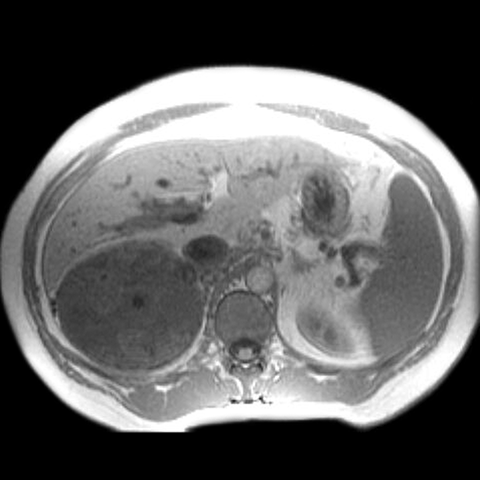

42-year-old-male presents with episodic headache, diaphoresis, and tachycardia. [2 of 3]